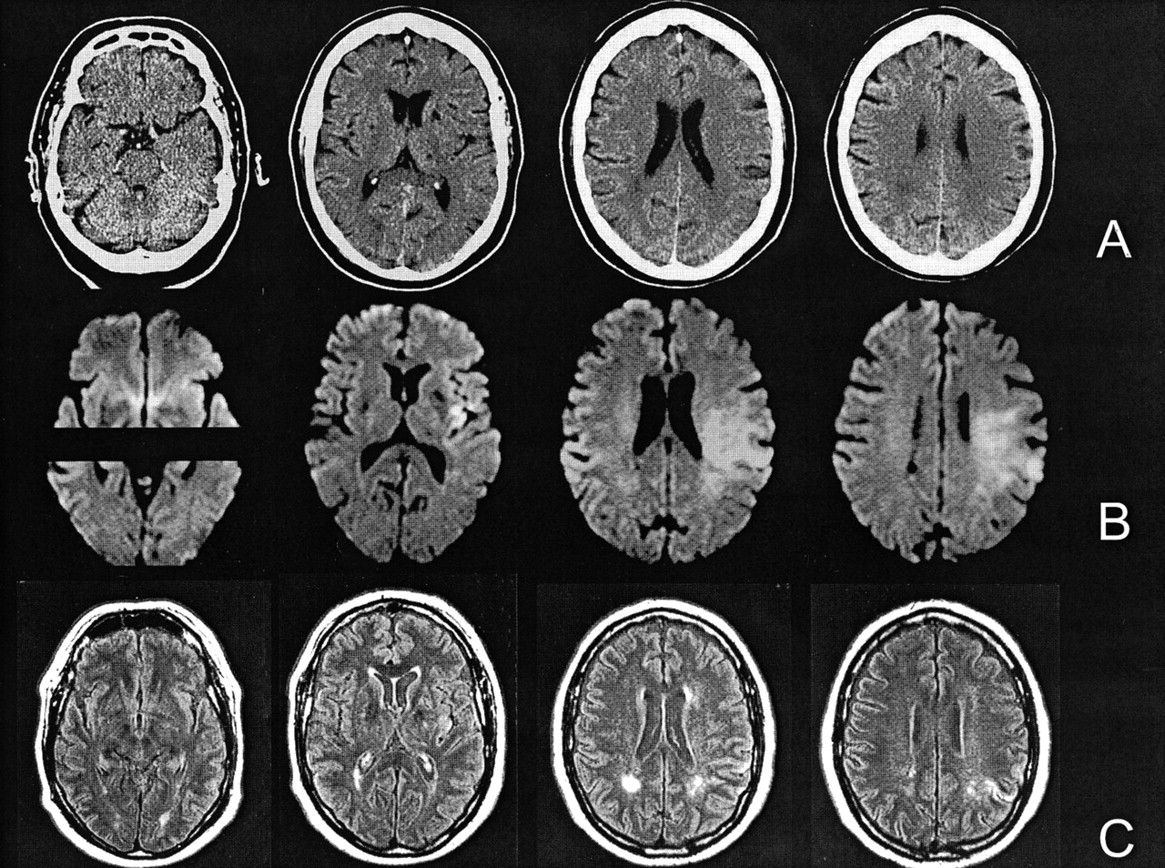

كشف اطباء اخصائيون في الاشعة التشخيصية، عن الاسباب التي تقف وراء ظهور نقاط بيضاء في الرنين المغناطيسي الذي يجرى على الدماغ.

وقال الاطباء أن الكثير من المرضى يتسائلون عن وجود نقاط بيضاء في رنين الدماغ، وهذا السؤال ليس من الممكن ان يتم الاجابة عنه دون تقييم المريض وفحصه سريرياً وبدّقة، وتحديد شكل وموقع النقاط داخل الدماغ وحجمها، وقد نحتاج لبعض الفحوصات والتحاليل.

وحدد الاطباء مجموعة من أسباب هذي النقاط وهي:

ــ نقاط بيضاء حميدة ليست ذي اهمية سريرية.

ــ الصداع النصفي/الشقيقة.

ــ ضربات الرأس وحوادث السير.

ــ تصلب الأعصاب.

ــ التهاب القشرة الدماغية.

ــ الخُراج الدماغي.

ــ الأورام الدماغية.

ــ إلتهاب الشرايين الدماغية الروماتيزمي.

ــ نقص التروية الدماغية نتيجة أمراض الضغط و السكر أو التدخين.

ــ أمراض المادة البيضاء الجينية و الوراثية.